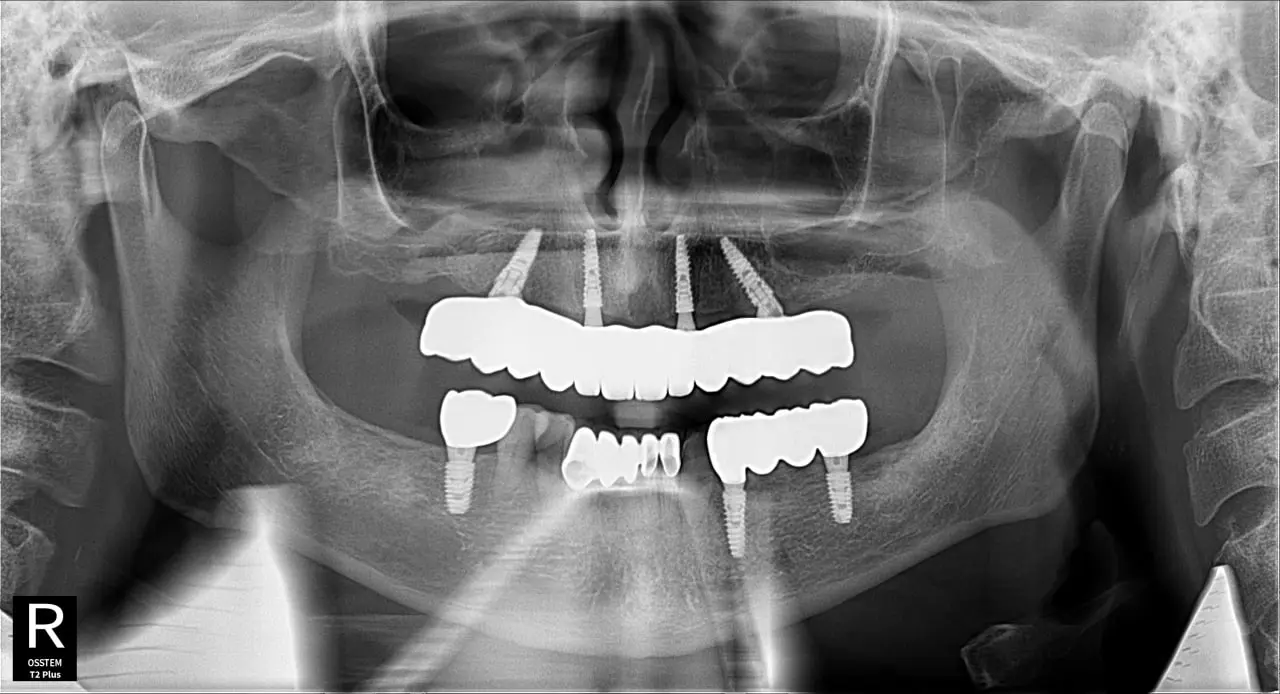

Наші роботи

Встановлення зубного імпланта у Млинові